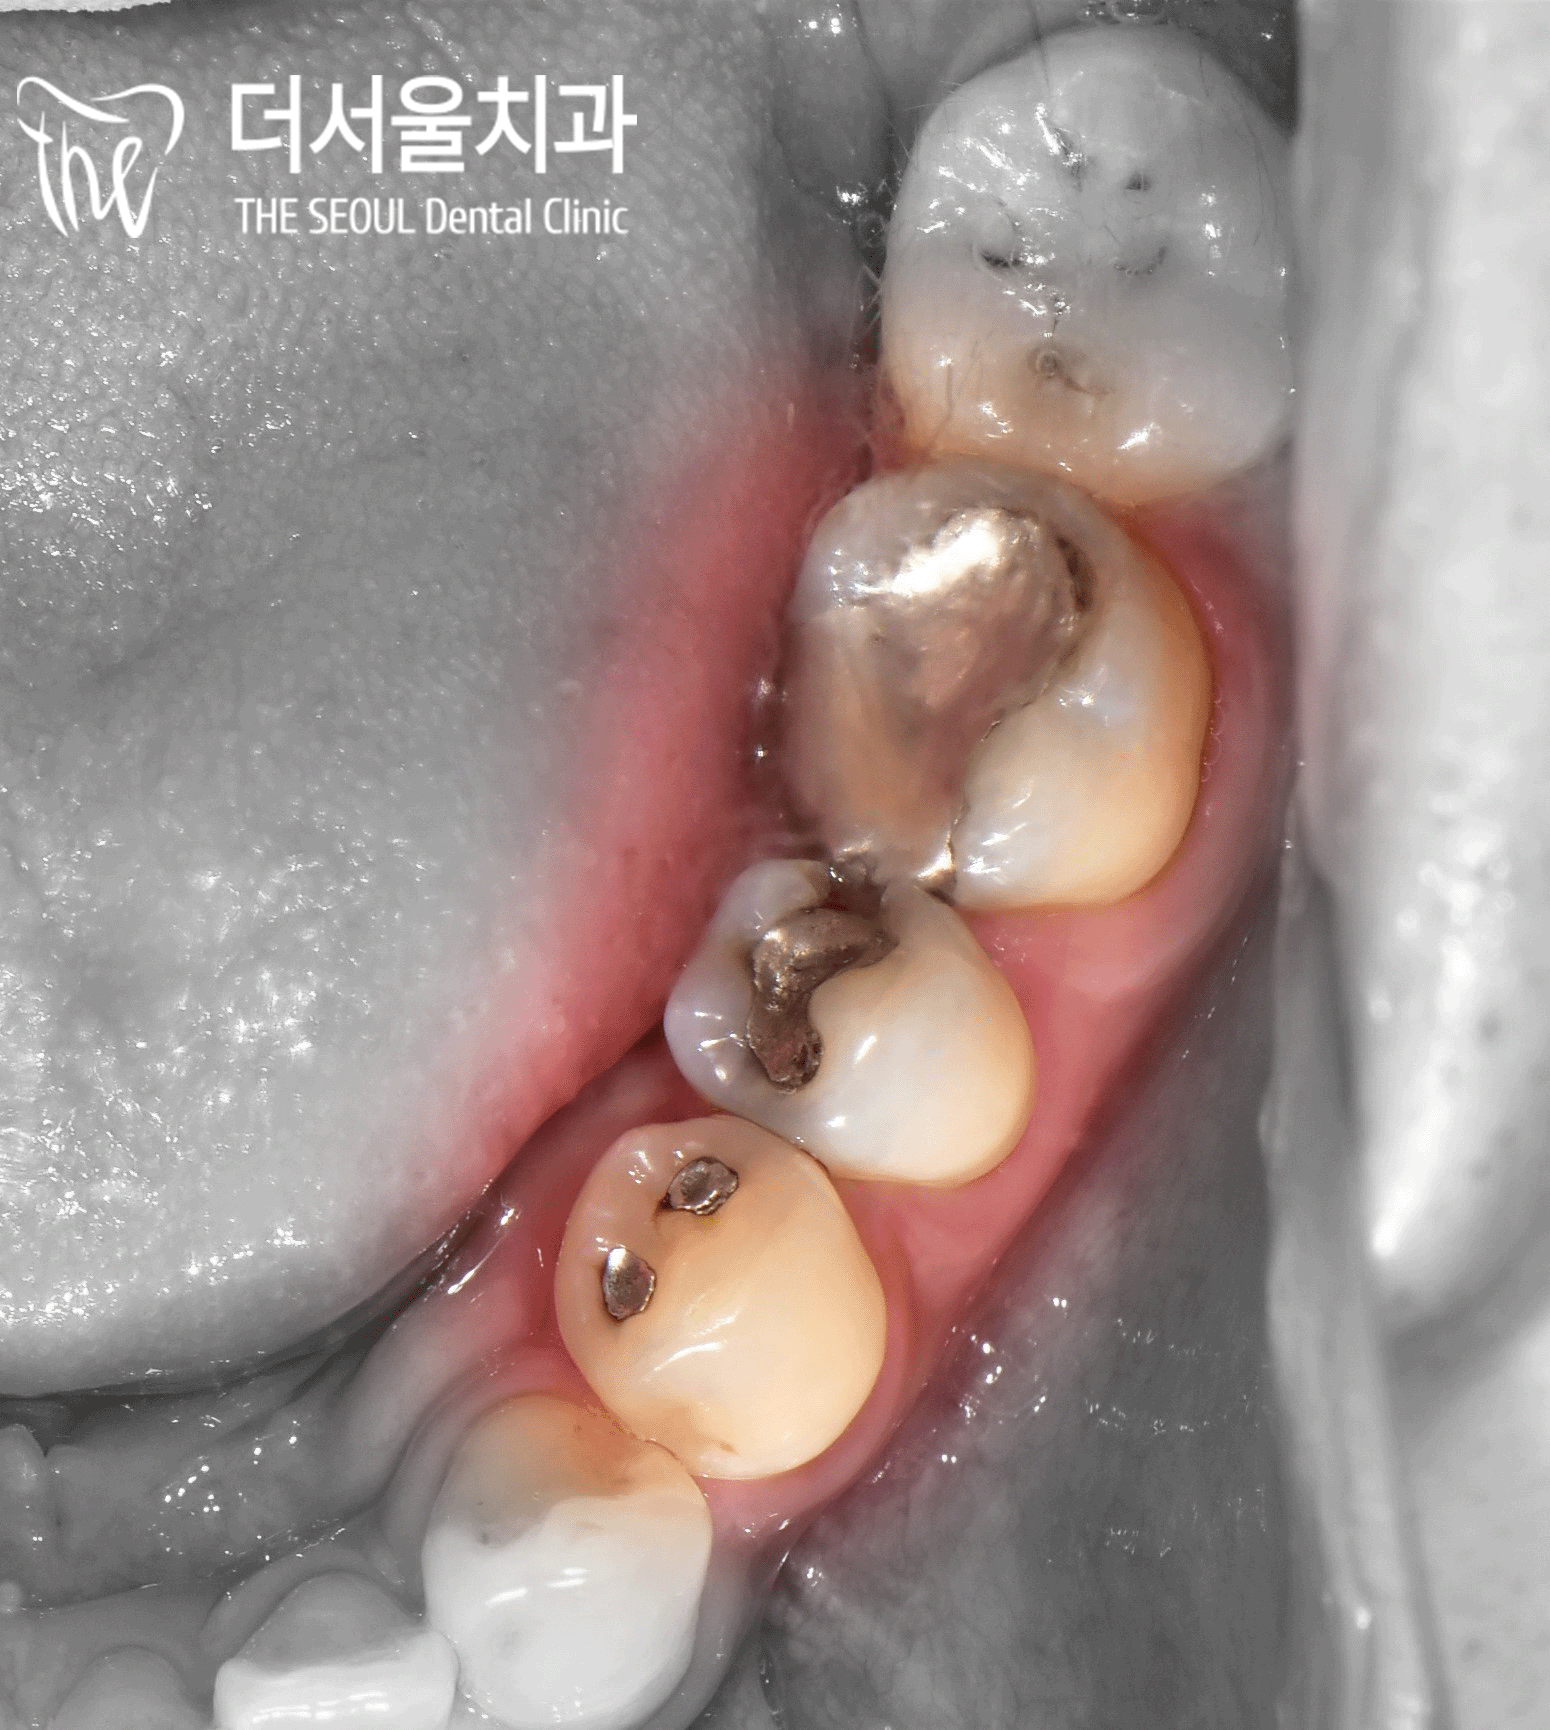

육안으로 살펴본 결과,

통증을 느끼고 있던 작은 어금니를 비롯해

인접한 치아에도 아말감이 씌워져 있었습니다.

딱 봐도 심미적으로 별로 좋지 않죠?ㅎㅎ